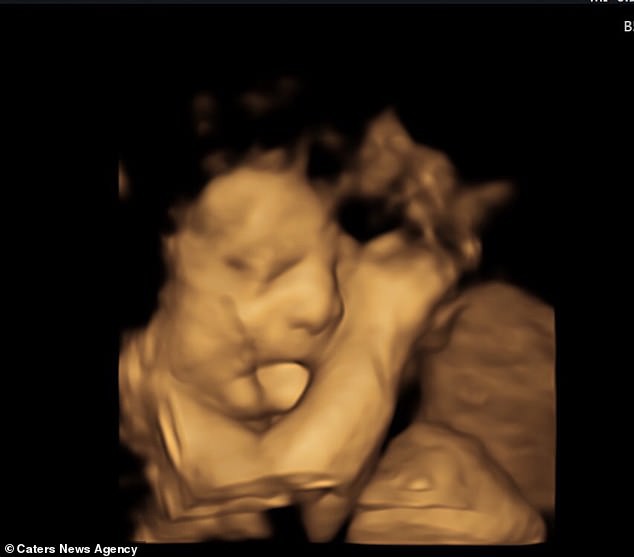

03/01/2019 22:55Siêu âm thấy con thè lưỡi vô cùng đáng yêu nhưng đến ngày con chào đời, bố mẹ không tin nổi vào mắt mình

Siêu âm thấy con thè lưỡi dễ thương, không ngờ bé mắc chứng bệnh hiếm gặp

Đi siêu âm ở tuần thai thứ 27, cả bác sĩ lẫn bố mẹ bé Baker là Farrah và Sean (42 và 41 tuổi, đến từ Jenks, Oklahoma, Hoa Kỳ) đều tin rằng cậu bé đang thè lưỡi để lộ vẻ tinh nghịch, đáng yêu và rất thích thú lưu lại hình ảnh đó.

Mẹ của bé - Farrah Roth chia sẻ: "Tôi luôn nghĩ thật dễ thương khi con thè lưỡi ra như thế qua hình ảnh siêu âm. Tôi thậm chí còn chia sẻ trên mạng về hình ảnh dễ thương đó".

Chỉ tới lúc chào đời bằng phương pháp sinh mổ sớm hơn 8 tuần so với dự sinh, bác sĩ mới nhận ra Baker mắc Hội chứng Beckwith - Wiedemann (BWS), một rối loạn phát triển quá mức hiếm gặp khiến lưỡi phát triển quá mức. Bên cạnh chiếc lưỡi lớn gấp đôi kích cỡ lưỡi thông thường ở các bé sơ sinh, Baker còn phải chịu đựng nhiều vấn đề sức khỏe khác.

Triệu chứng của BWS khác nhau tùy theo từng cá nhân nhưng nó có thể tác động tới lưỡi, các cơ quan ở bụng, da ở gần tai, thận và chiều cao. Mẹ bé Baker cho biết thêm: "Sau khi con chào đời, một trong những điều đầu tiên bác sĩ nói với chồng tôi là: 'Con có cái lưỡi rất to'. Nhưng không có các dấu hiệu khác của BWS ngoài việc tai bé hơi lõm vào ở phần dái tai. Có thể nói, lưỡi con to gấp đôi kích cỡ lưỡi thông thường. Nó cũng dày hơn nhiều. Nếu con rút lưỡi vào trong miệng thì bên trong chẳng còn khoảng trống nào hết. Vì vậy, lưỡi con thường xuyên thè ra ngoài và che khuất phần môi dưới của con".